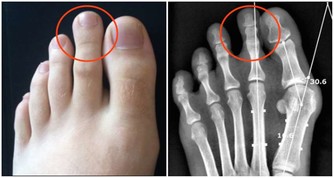

2、腰椎間盤突出

腰椎病是青壯年女性腰痛的常見病因。多由於腰部受傷、長期慢性勞損引起,表現為腰部的疼痛,下肢的放射性疼痛麻木等,治療有臥床牽引、手術等。